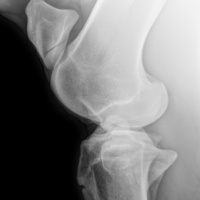

RADIOLOGIA DIGITALE AD ALTA DEFINIZIONE

Cuattro DR HD è l'ultimo sistema radiografico digitale ad alta definizione per piccoli animali ed equini prodotto dal fornitore leader di soluzioni radiografiche digitali veterinarie.

Innovativo, veloce, efficace, sicuro e ancora più brillante: l'ultimo sistema a raggi X, Cuattro DR HD soddisfa i più alti standard nella diagnostica radiografica veterinaria.

- Visualizza i dettagli come mai fino ad ora : 17x17'’ 100 microns High definition detectors combinati con la migliore tecnologia post-elaborazione nel nostro software per immagini di altissima qualità